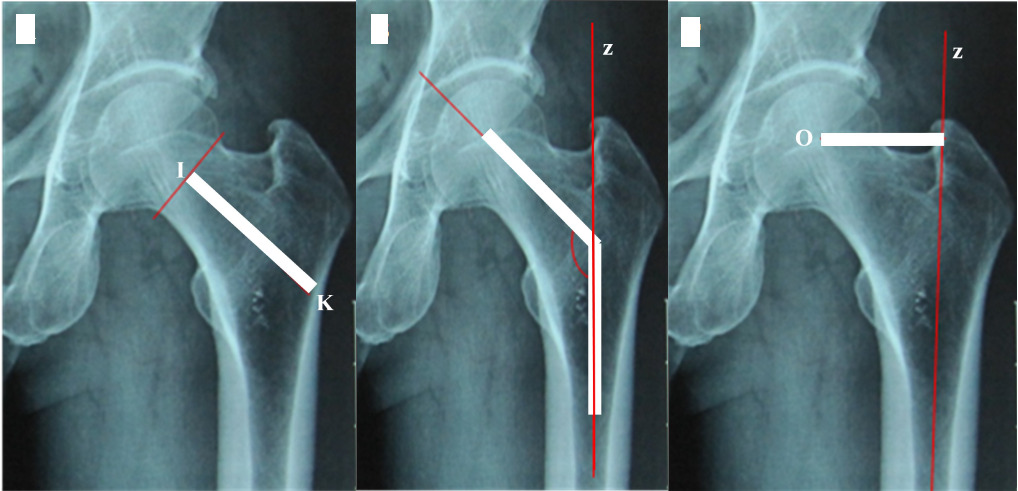

Indicators related to the selection and placement of Spiron joint shafts

- Distance between the base of the head (close to the head) and the inner edge of the lateral femoral wall (along the mid-axis of the femoral neck): Is the distance between points I and K (Figure 3A). Point I represents the XY segment’s midpoint, while point K represents the intersection of the longitudinal axis between the femoral neck and the inner edge of the lateral femoral wall.

- The femoral neck angle is the angle formed by the axis of the neck (Line IK) and the anatomical axis of the femoral shaft (Line z) (Figure 3B).

- The offset is the distance from the center of the head to the anatomical axis of the femur. Is the distance between point O (the centre of the head) and line z (Figure 3C).